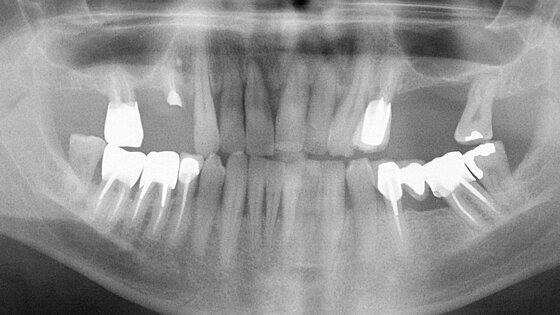

Il s’agit d’un patient, ancien fumeur, âgé de 51 ans au début du traitement. Ce patient présente une hypertension artérielle stabilisée, il est sous Kardégic® pour un infarctus en 2005. Ce patient souhaite une réhabilitation fixe au maxillaire. Ses motivations sont à la fois d’ordre fonctionnel et esthétique (Figs. 1a et 1b).

L’état parodontal des dents restantes ne permet pas d’envisager leur conservation. Toutes les dents maxillaires sont extraites de manière atraumatique, les alvéoles soigneusement curetées et une prothèse maxillaire amovible complète est mise en place le jour même. Après une période de cicatrisation, un dentascan permet d’évaluer le volume osseux disponible. Cet examen confirme une résorption osseuse importante dans les secteurs postérieurs du maxillaire (Figs. 2a–c) : SA4 dans la classification de C. Misch. Le volume osseux étant < 5 mm, la pose des implants sera différée de 5 à 6 mois après les comblements sinusiens, ceci afin d’obtenir une stabilité primaire suffisante.